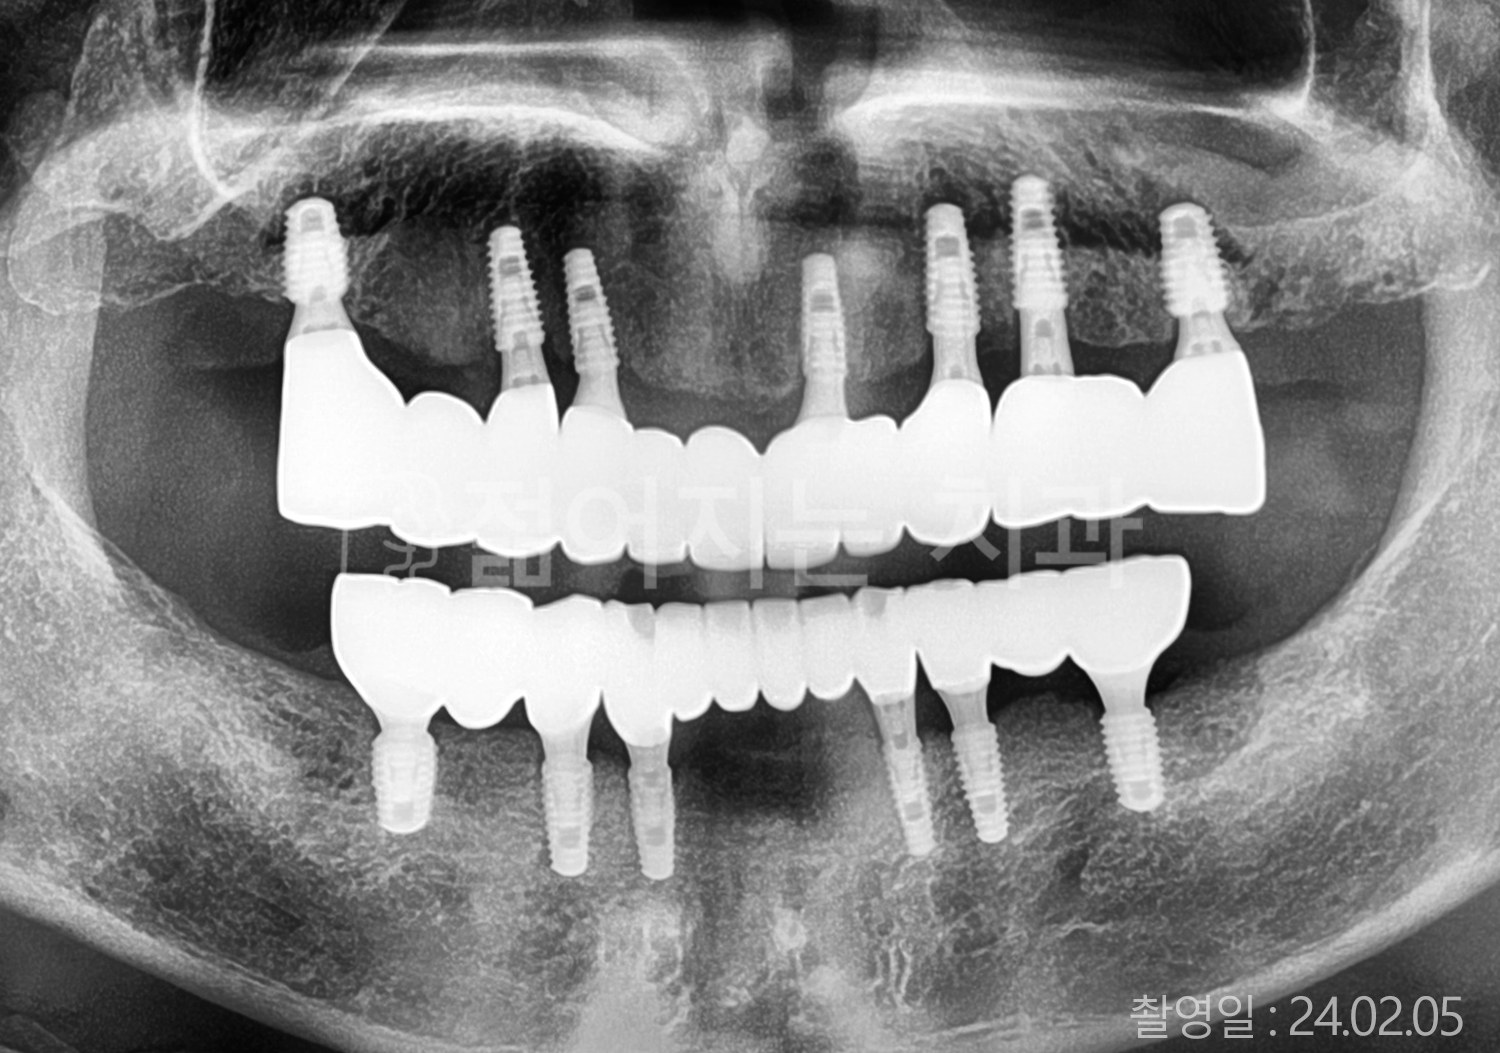

• 50대 전체치아 10개 이상 임플란트